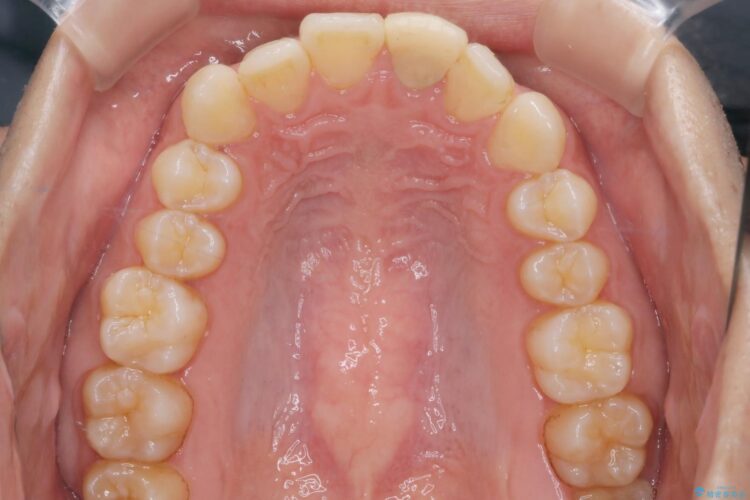

前歯の叢生と口元を下げたいとのことでご来院されました。

その上で今回は抜歯を行わず、歯の表面をわずかに整えるIPRを活用しながら、インビザラインで前歯のガタつきを優先的に改善していく計画を立案しました。

インビザライン矯正により、前歯のガタつきが改善されました。